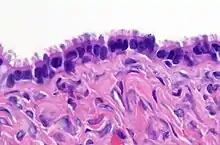

| Mucinous tumor | 15% | 8.8% | Benign mucinous tumors of the ovary consist of simple, nonstratified columnar epithelium with basally-located hyperchromatic nuclei and resemble gastric foveolar epithelium.[6] | ![]() | |